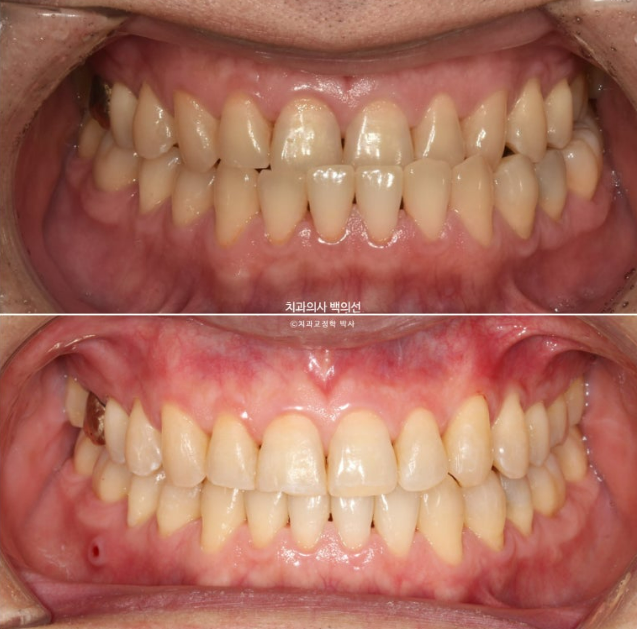

23년 12월 주걱턱 치료를 위해 오신 40대 환자분입니다.

골격적 주걱턱 뿐만 아니라 아래턱이 왼쪽으로 틀어진 비대칭도 보입니다.

23.12

앞니가 완전히 거꾸로 물립니다.

치열은 가지런한 편이나 앞니 반대교합으로 오랫동안 지내오면서 아래앞니에 부딫쳐 위 앞니 마모도가 심합니다.